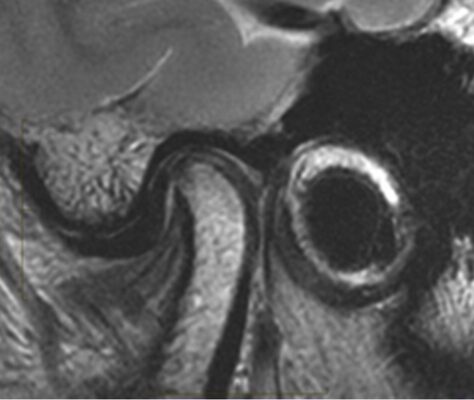

- MRI: là tiêu chuẩn vàng để lượng giá mô mềm trong TMJD. MRI có ưu điểm phân tích đĩa khớp, mô sau đĩa và các hệ cơ, cấu trúc dây chằng xung quanh theo ba mặt phẳng. MRI nên được xem xét khi có các triệu chứng lâm sàng bao gồm đau và tiếng lục cục khi vận động hàm hoặc nếu nghi ngờ có ung thư. MRI có độ nhạy 95% và độ đặc hiệu 88% khi so sánh với nội soi khớp để đánh giá TMJD.